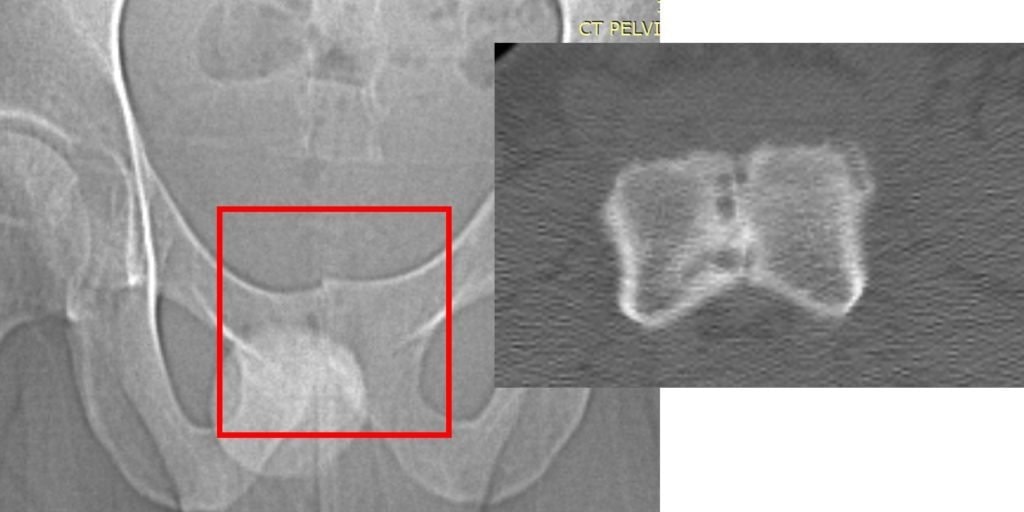

When the patient resumed running just two months after the fusion surgery, the stress that the SI joint would typically absorb was instead redirected to the symphysis pubis. This excessive strain led to the rapid onset of severe osteitis pubis. Imaging studies (X-ray and CT scan) revealed significant damage: the normal space within the symphysis pubis, which houses the fibrous disc, had disappeared entirely, and the surrounding bone exhibited marked erosion.

At this stage, the patient faced the prospect of another surgery—this time to address the osteitis pubis resulting from the initial procedure. Instead, he sought treatment from Dr. Markle, a physician in the licensed Regenexx network, where orthobiologic procedures were utilized to address the worsening condition of his symphysis pubis joint.

Fluoroscopy-guided imaging demonstrated the precise delivery of the patient’s own bone marrow concentrate into the deteriorating bone surrounding the symphysis pubis and into the degenerated joint itself. This approach designed to support healing, may help reduce inflammation, and may help promote stability in the affected area.

The images below, taken several months after the orthobiologic procedure, demonstrate significant improvement in the condition of the symphysis pubis joint.

The follow-up images indicate a restored joint space in the symphysis pubis, with improvements in the surrounding bone structure. The patient reported noticeable improvement, noting that 80–90% of his symptoms had diminished and that he experiences minimal daily discomfort. This outcome illustrates the potential role of orthobiologic procedures in supporting joint health and function.